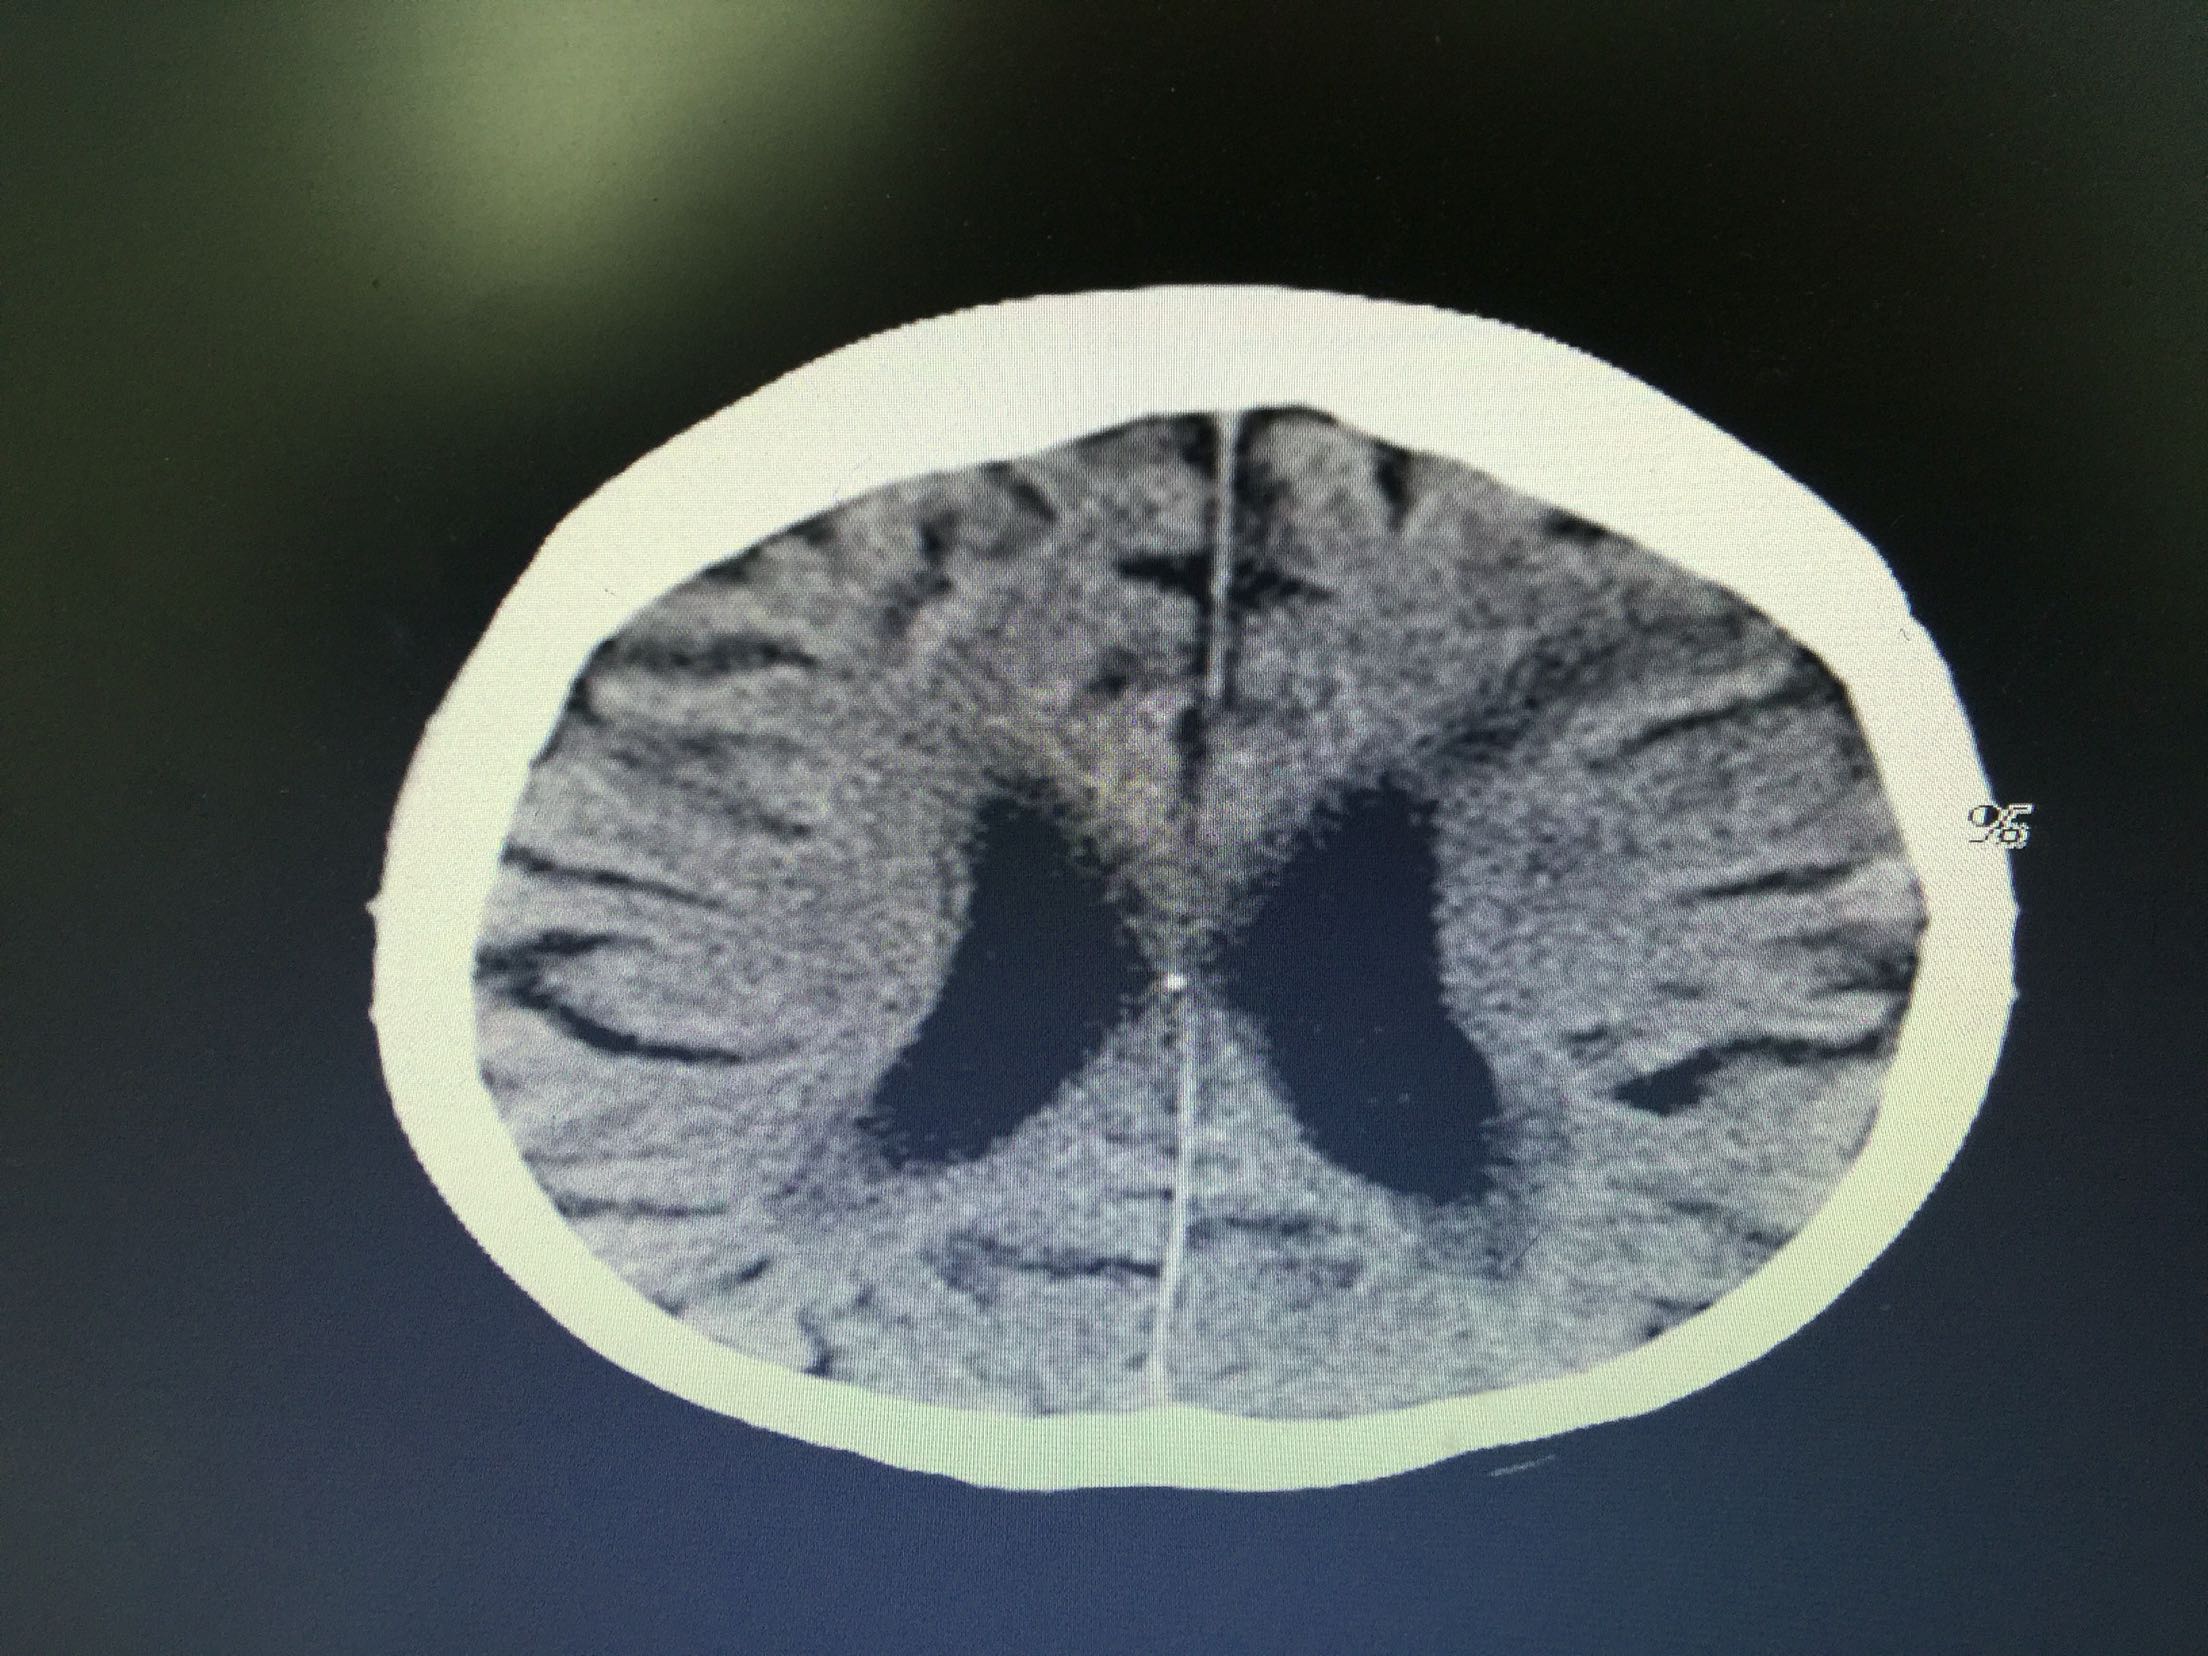

分水岭梗塞1例!

女,86岁,以“嗜睡、右侧肢体无力20小时”入院。 现病史:20小时前无诱因出现嗜睡,可唤醒,问话可答,不理解含义,右侧肢体无力。 既往史:高血压。

查体:血压:136/80mmHg,意识清,不全运动性失语,右侧中枢性面瘫,右侧肢肌力1级,Babinski征左-右+。

诊断:分水岭梗塞! 治疗:扩容、抗板、稳定斑块、促进侧枝建立等治疗。